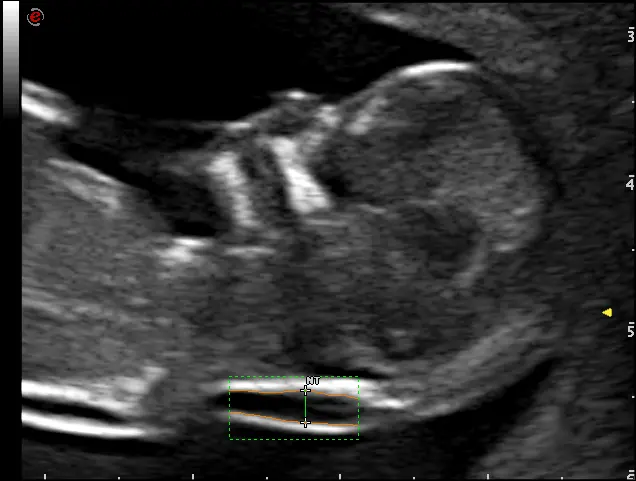

MyLab™Sigma - Umbelical cord PW Doppler mode

MyLab™Sigma - Umbelical cord PW Doppler mode